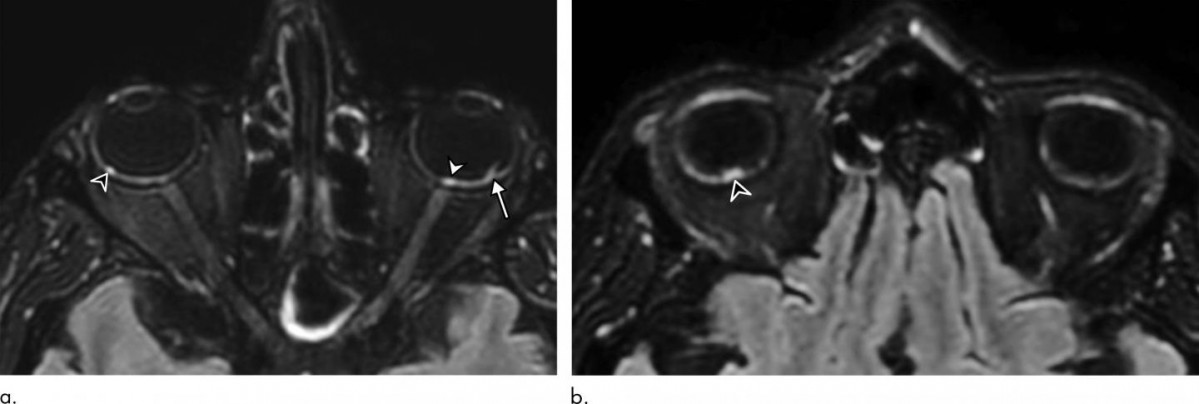

De los 129 pacientes, nueve (7%) tenían hallazgos anormales en la resonancia magnética del globo ocular. Las resonancias magnéticas mostraron uno o más nódulos en la parte posterior, o polo posterior, del globo ocular. Ocho de los nueve pacientes habían pasado un tiempo en la unidad de cuidados intensivos (UCI) por COVID-19.

"Demostramos que algunos pacientes con COVID-19 grave de la cohorte francesa de COVID-19 tenían uno o varios nódulos en el polo posterior del globo --destaca el autor principal del estudio, Augustin Lecler, profesor asociado de la Universidad de París y neurorradiólogo del Departamento de Neurorradiología del Hospital Fundación Adolphe de Rothschild de París--. Esta es la primera vez que se describen estos hallazgos mediante resonancia magnética".

Los nueve pacientes tenían nódulos en la región macular, el área en la parte posterior del ojo responsable de nuestra visión central. Ocho tenían nódulos en ambos ojos.